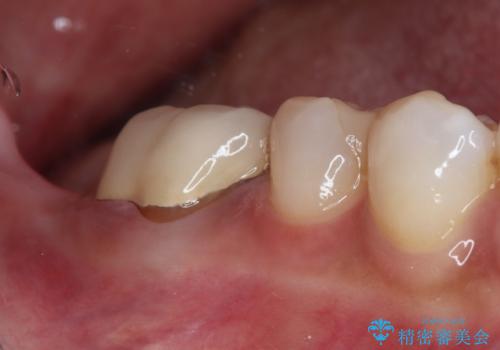

右下の欠損部を長期間欠損を放置していたことで、咬み合う上の奥歯が動いてしまっていたので、まずは上顎奥歯の部分矯正を行うこととしました。

理想的な咬み合わせに改善した上で、インプラント補綴治療を行うこととしました。

部分矯正を行ったこと治療期間は長くなりましたが、違和感のない咬み合わせを達成することができました。